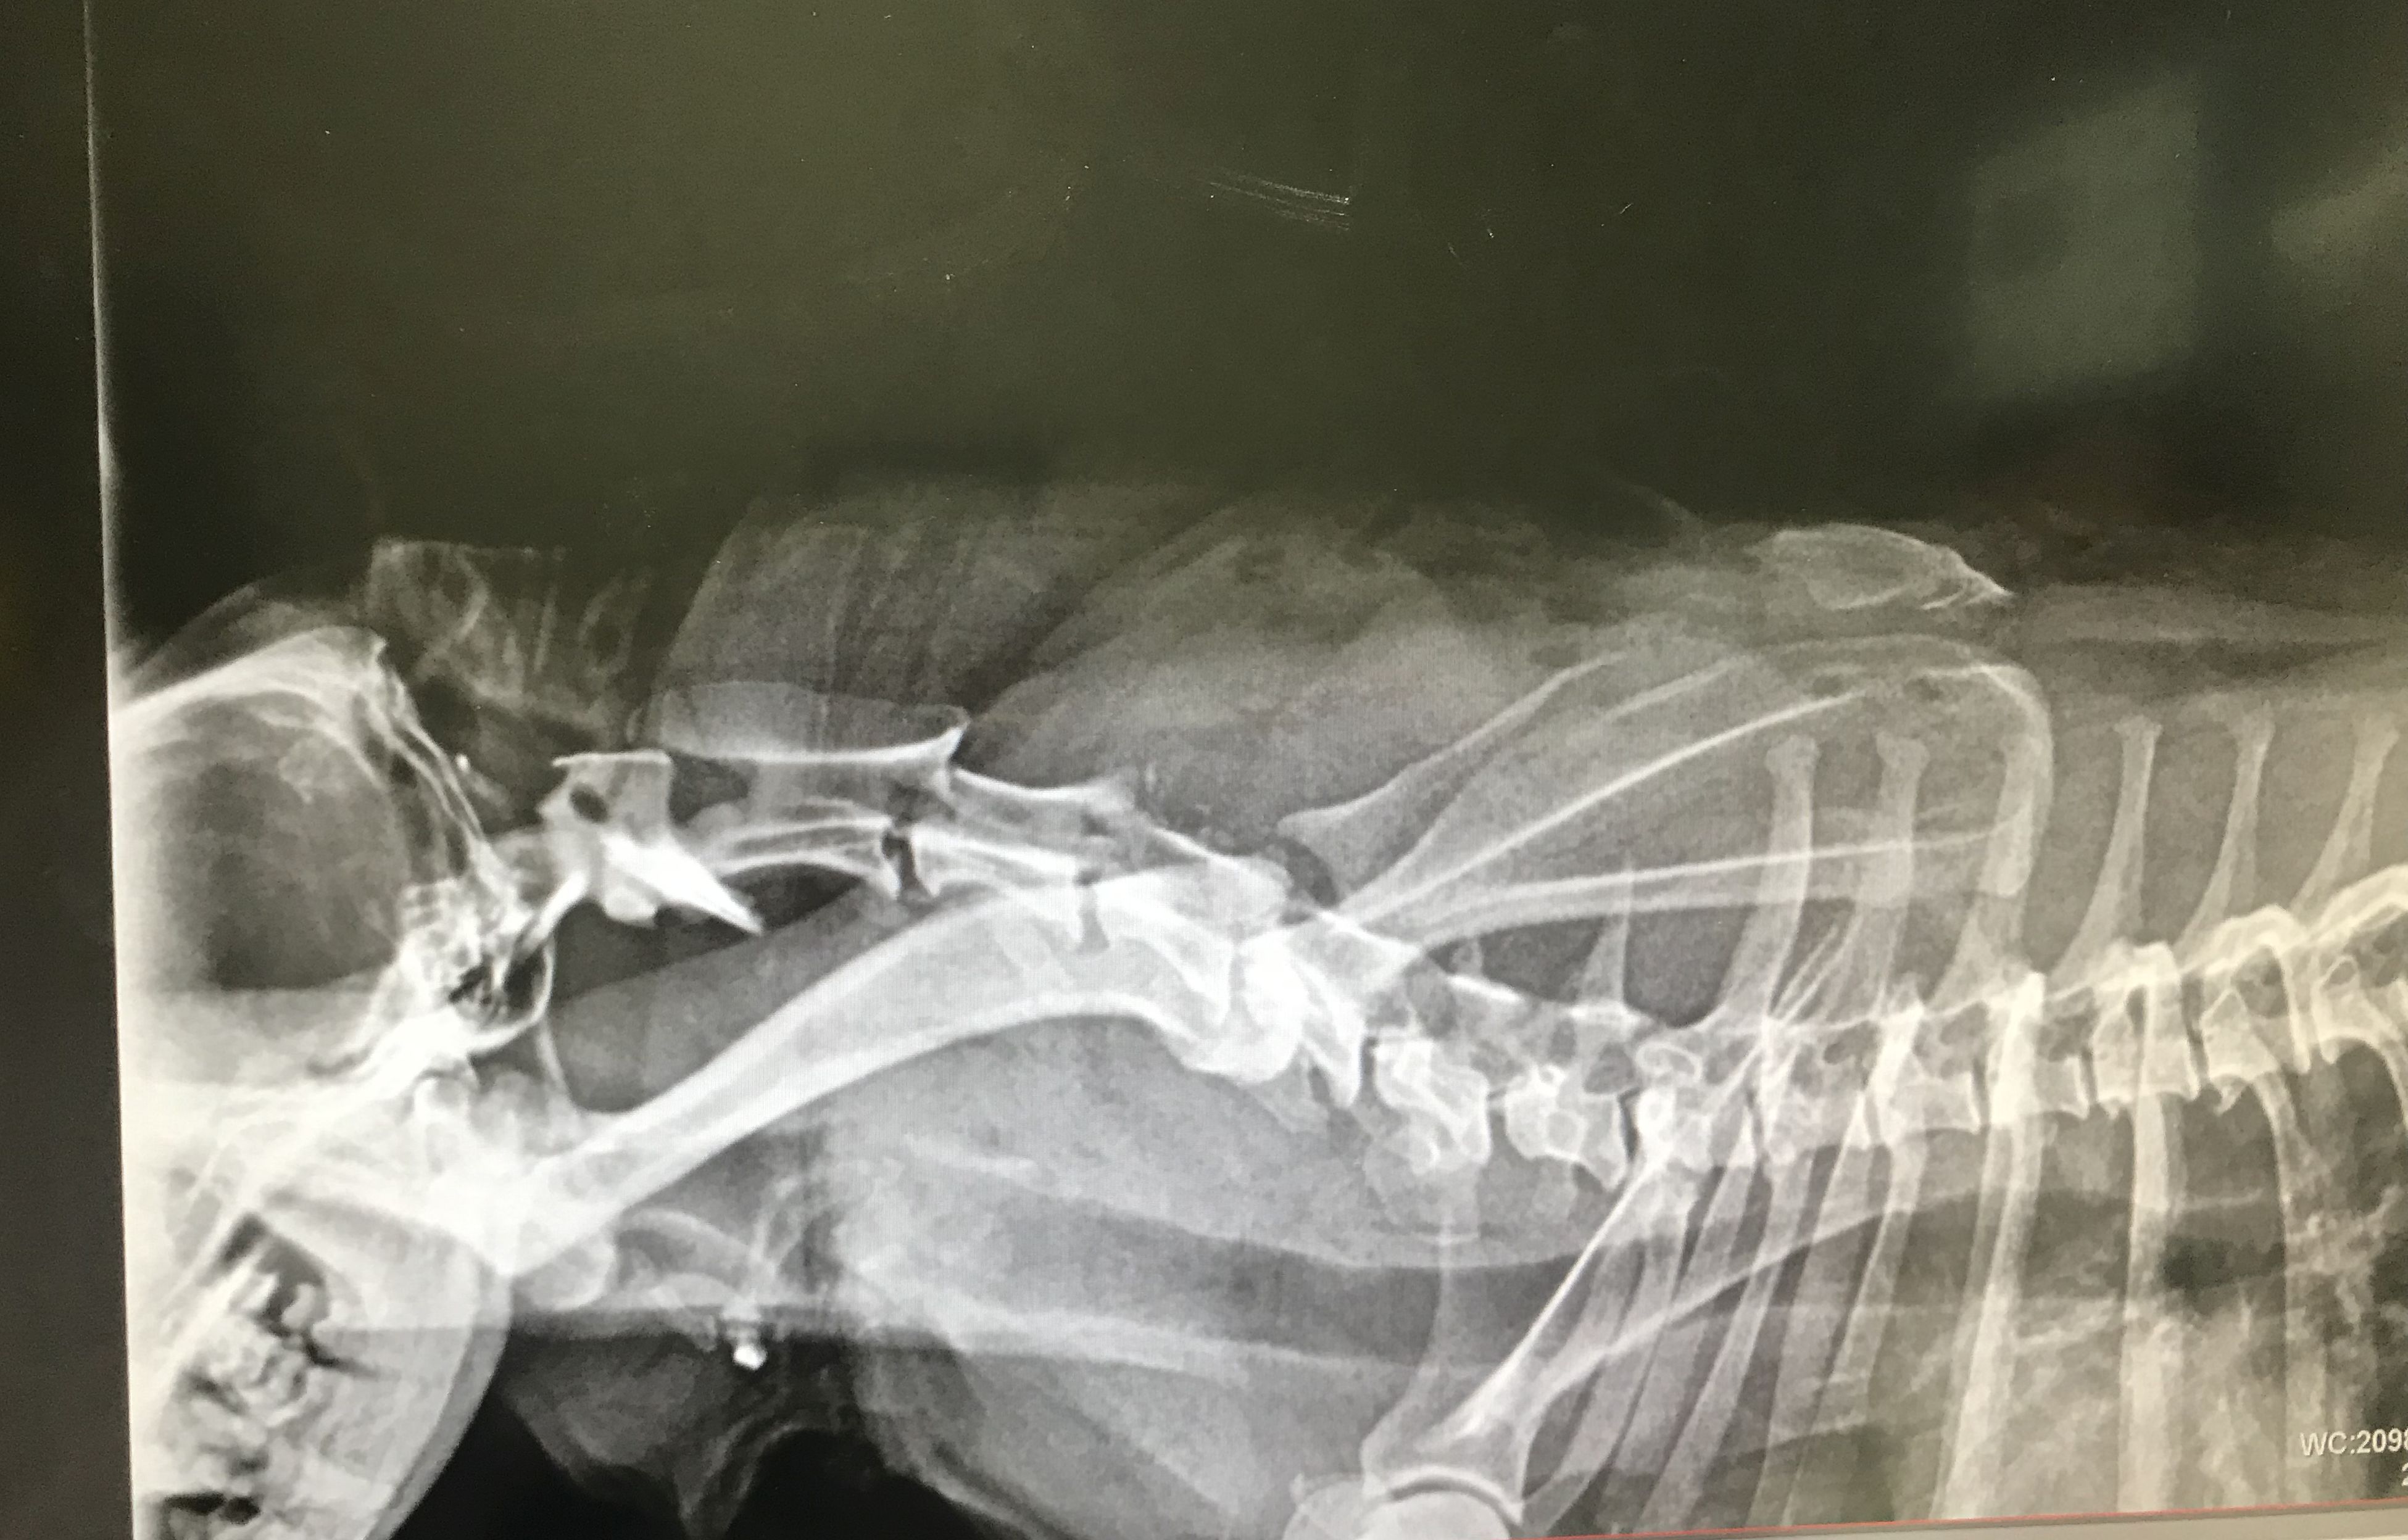

Rufus, a six year old miniature Doberman Pinscher, was attacked by a Bullmastiff near their home, while walking with his owner Arlene on August 14, 2019.